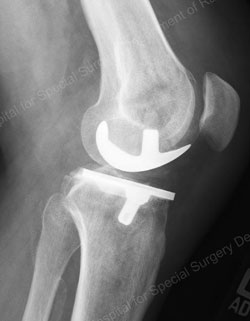

Figure: Example of a fixed bearing unicondylar knee replacement

(the images on top represent a preoperative joint; the images on the bottom represent a postoperative joint)